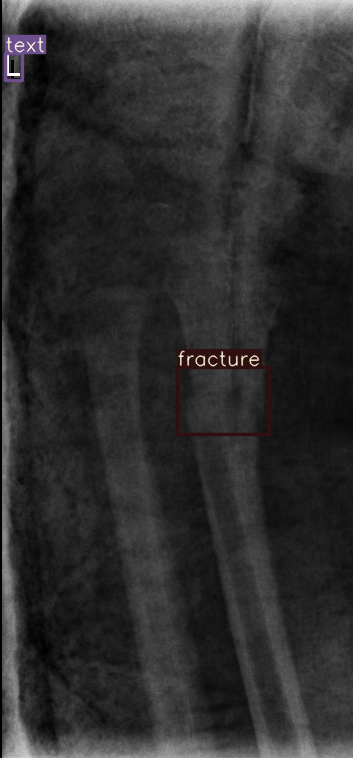

Figure 8: Sample of five images from the GRAZPEDWRI-DX test set, displaying ground-truth and predicted bounding box annotations: (a-e): ground-truth annotations, (f-j): YOLOv11l annotations, and (k-o): G-YOLOv11 annotations.

Table 4: Confidence scores predicted by YOLOv11l and the proposed G-YOLOv11l detectors for five images from the GRAZPEDWRI-DX test set, PR: pronator sign, FP: False positive.

Figure number Class name Confidence score predicted Confidence score predicted

by YOLOv11l by our G-YOLOv11l

8(a) soft tissue, fracture, metal, text -, 0.670.67, 0.860.86, 0.830.83 -, 0.700.70, 0.890.89, 0.840.84

8(b) fracture, text 0.780.78, 0.710.71 0.790.79, 0.730.73

8(c) fracture, text 0.820.82, 0.780.78 0.810.81, 0.790.79, (FP: pr 0.44)0.44)

8(d) fracture, fracture, text 0.770.77, 0.700.70, 0.880.88 0.760.76, 0.520.52, 0.890.89

8(e) fracture, periosteal reaction, text 0.760.76, 0.690.69, 0.760.76 0.750.75, 0.600.60, 0.760.76

The results in Table 4, derived from Figure 8, compares the confidence scores predicted by YOLOv11l and G-YOLOv11l detectors for five test images from the GRAZPEDWRI-DX dataset. Figure 8 contrasts ground-truth annotations with predictions from YOLOv11l and G-YOLOv11l. G-YOLOv11l shows slight improvements, such as higher confidence scores for "fracture" and "metal" in Figure 8(a) (0.700.70 and 0.890.89 vs. 0.670.67 and 0.860.86) and for "text" in Figure 8(b) (0.730.73 vs. 0.710.71). However, limitations include false positives, such as for "pronator sign" in Figure 8(c) (score 0.440.44), and lower confidence for some instances, as seen in Figures 8(d) and 8(e). While G-YOLOv11l demonstrates competitive performance, further refinements are required to improve its robustness.